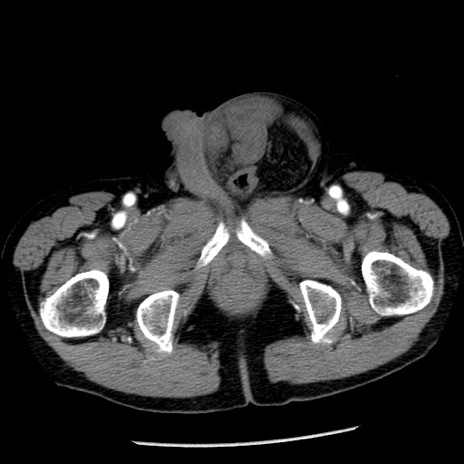

冠状断像

症例26(横断像)

【症例】80歳代男性

【主訴】嘔吐

【現病歴】昨晩2回嘔吐あり、今朝になっても嘔吐あり。来院。

【既往歴】胃潰瘍

【身体所見】意識清明、BT 37.6℃、BP 166/95mmHg、HR 100bpm、SpO2 97%、腹部:平坦・軟、腸蠕動音聴取良好、圧痛なし。

【データ】WBC 21900、CRP 1.46